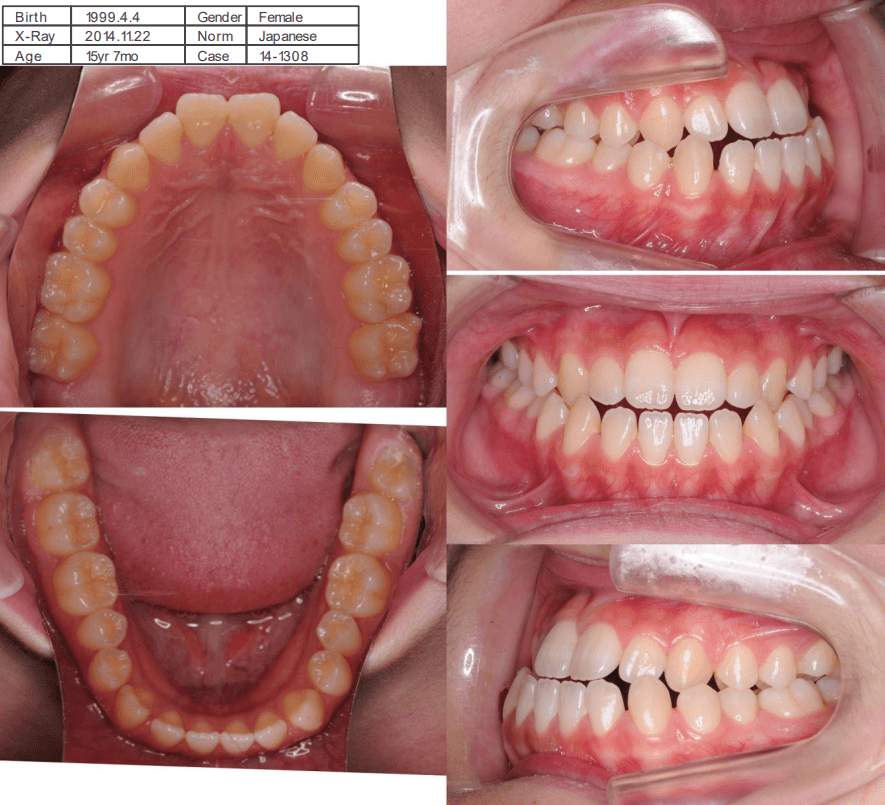

| 年齢・性別 | 15歳の女性 |

|---|---|

| 主訴 | 咬み合わせが逆であること(反対咬合)を気にされて来院された15歳7か月の女性。見た目や機能面の改善を希望されていました。 |

| 治療期間・回数 | 4年4ヶ月・28回 |

| 費用 | 900,000円 |